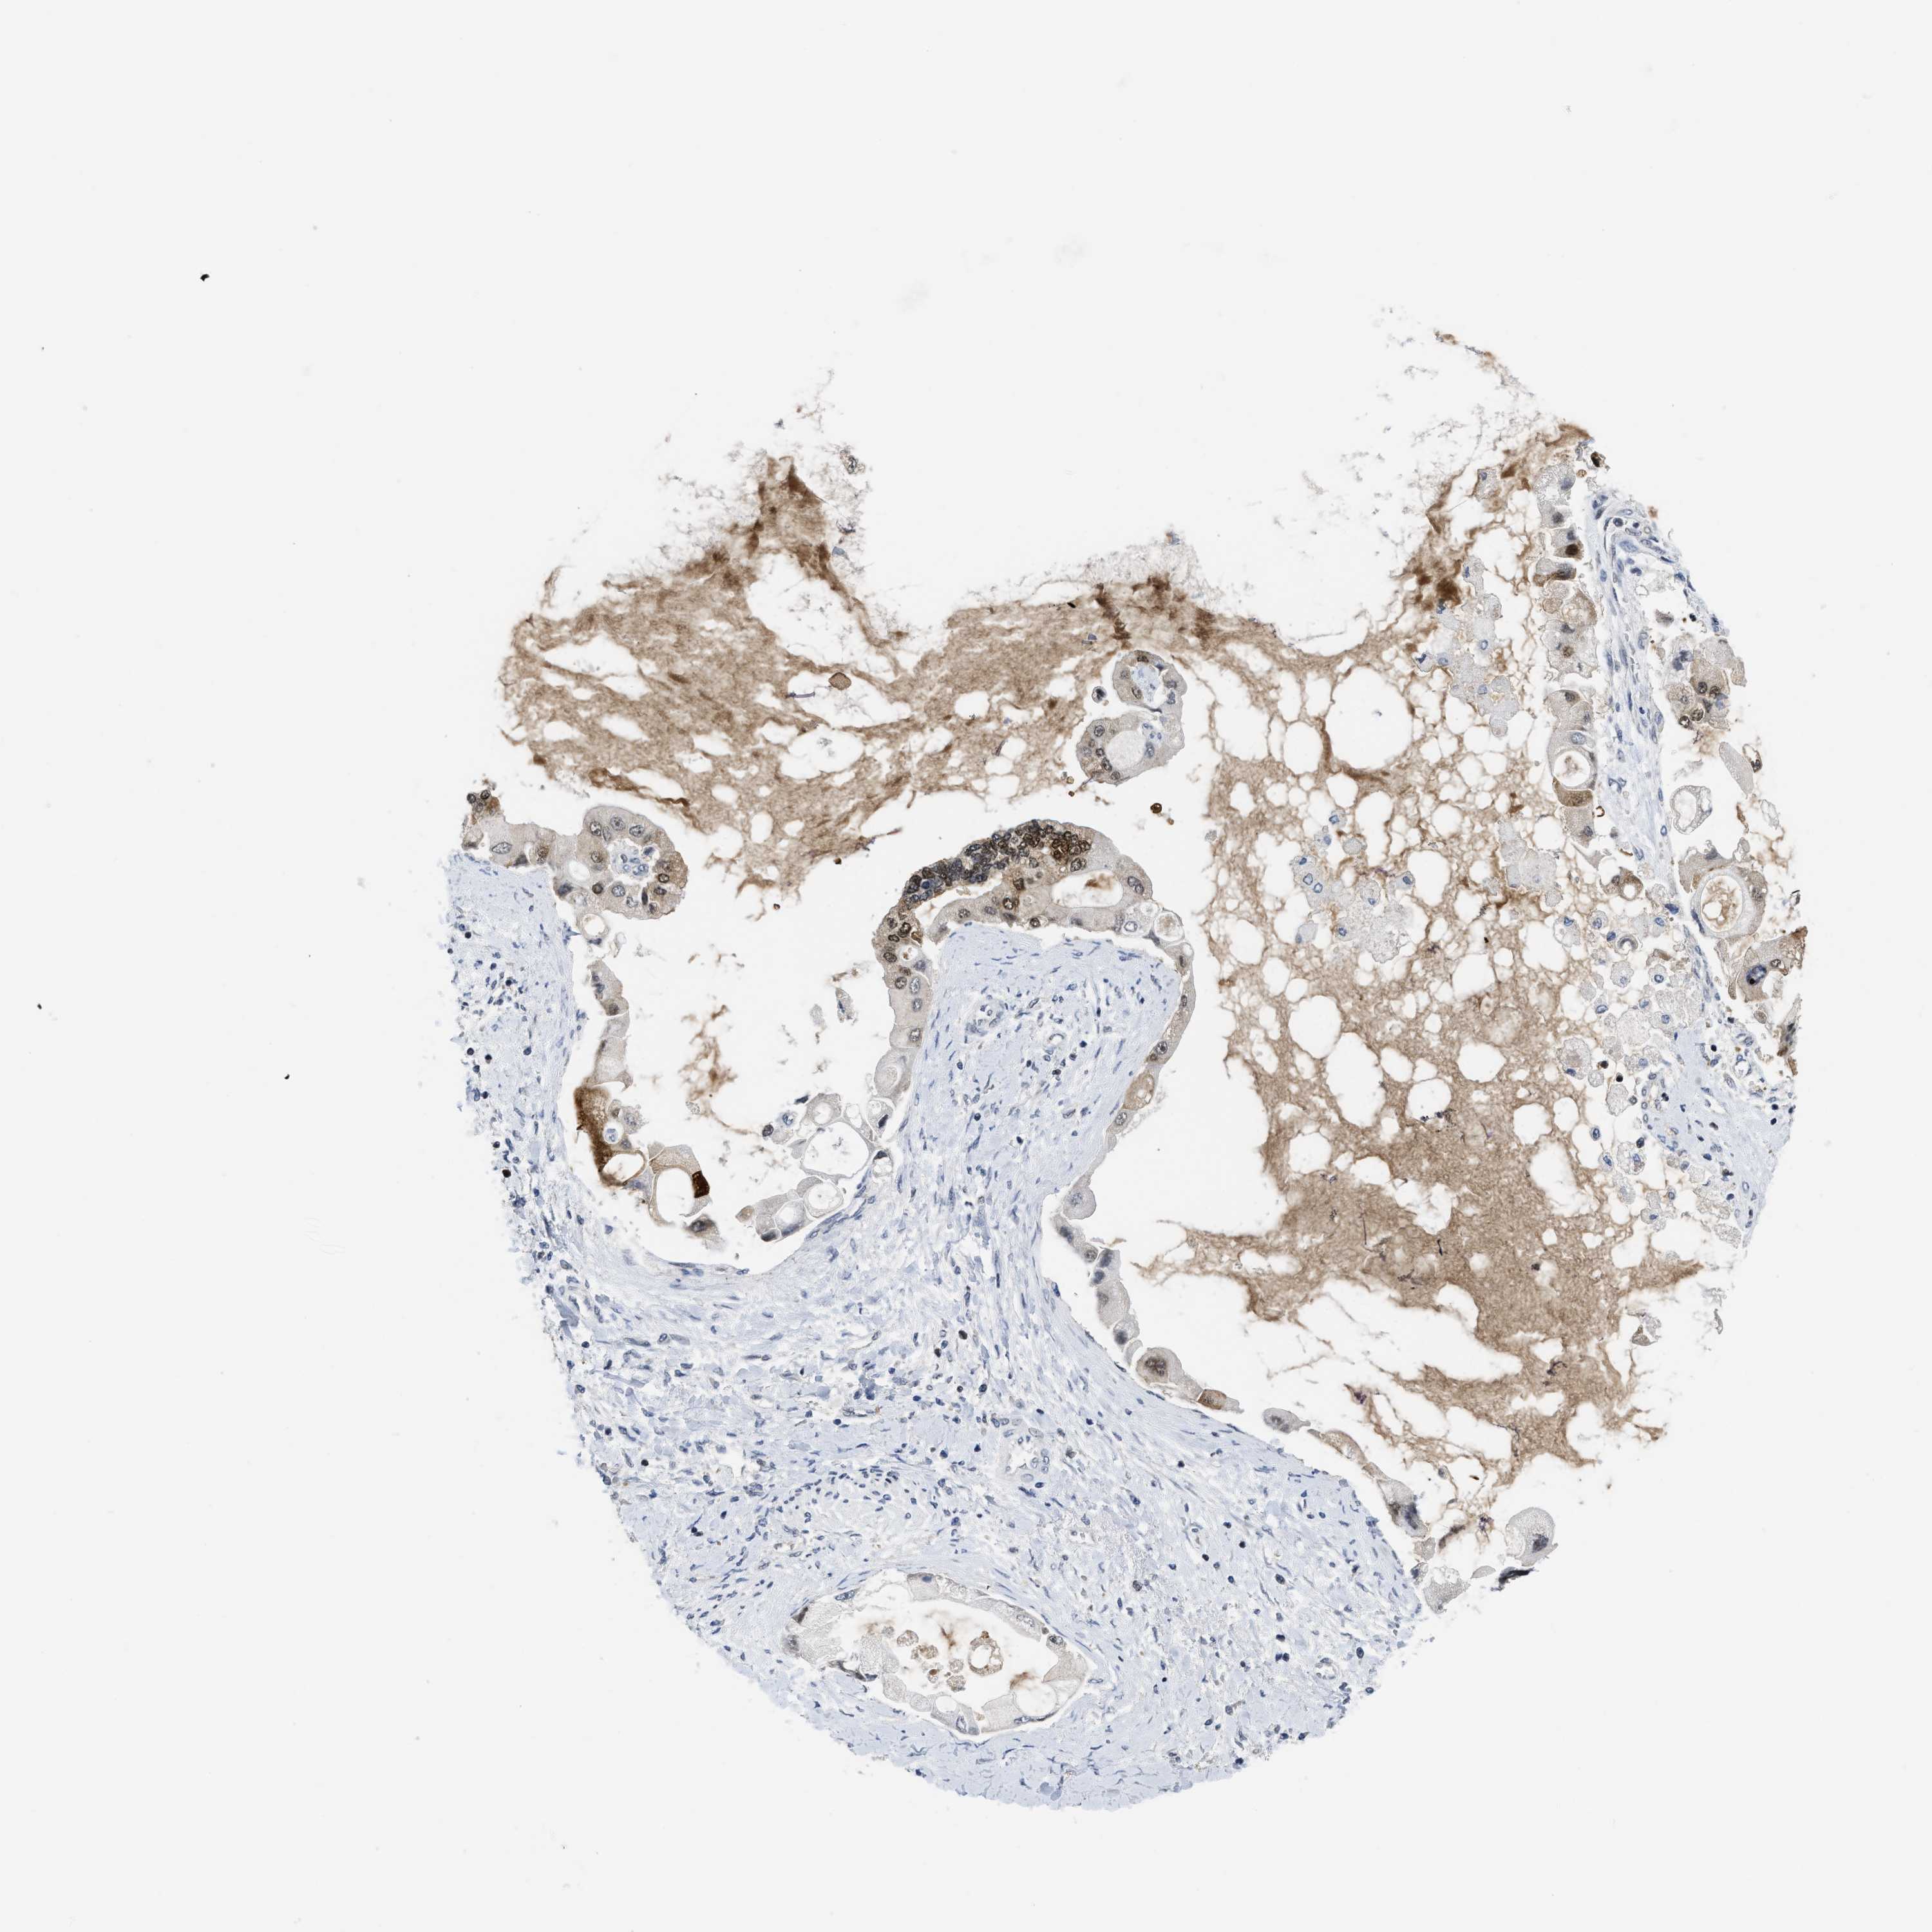

LIVER CANCER - Protein expressioni

A mouse-over function shows sample information and annotation data. Click on an image to view it in a full screen mode. Samples can be filtered based on level of antibody staining by selecting one or several of the following categories: high, medium, low and not detected. The assay and annotation is described here.

Note that samples used for immunohistochemistry by the Human Protein Atlas do not correspond to samples in the TCGA dataset.

Antibody stainingi

Antibody staining in the annotated cell types in the current human tissue is reported as not detected, low, medium, or high, based on conventional immunohistochemistry profiling in selected tissues. This score is based on the combination of the staining intensity and fraction of stained cells.

Each image is clickable and will lead to virtual microscopy that enables deeper exploration of all samples and also displays staining intensity scores, fraction scores and subcellular localization as well as patient and tissue information for each sample.

Antibody HPA001275

Antibody CAB017442

Staining

High

Medium

Low

Not detected

Intensity

Strong

Moderate

Weak

Negative

Quantity

>75%

75%-25%

<25%

None

Location

Nuclear

Cytoplasmic/membranous

Cytoplasmic/membranous,nuclear

Carcinoma, Hepatocellular, NOS

Cholangiocarcinoma